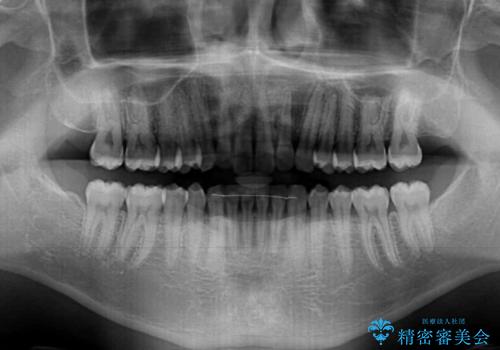

細かい隙間にものがはさまる インビザラインによる矯正治療

- 上下の前歯の隙間を気にして来院された患者様です。

インビザラインを用い、上下歯列のスペースを閉じていくこととしました。

銀行にお勤めのため、突然の転勤により通院が大変な状況となりましたが、インビザラインであれば2-3ヶ月に1度を目安に来院いただき、無事に治療を終えることができました。